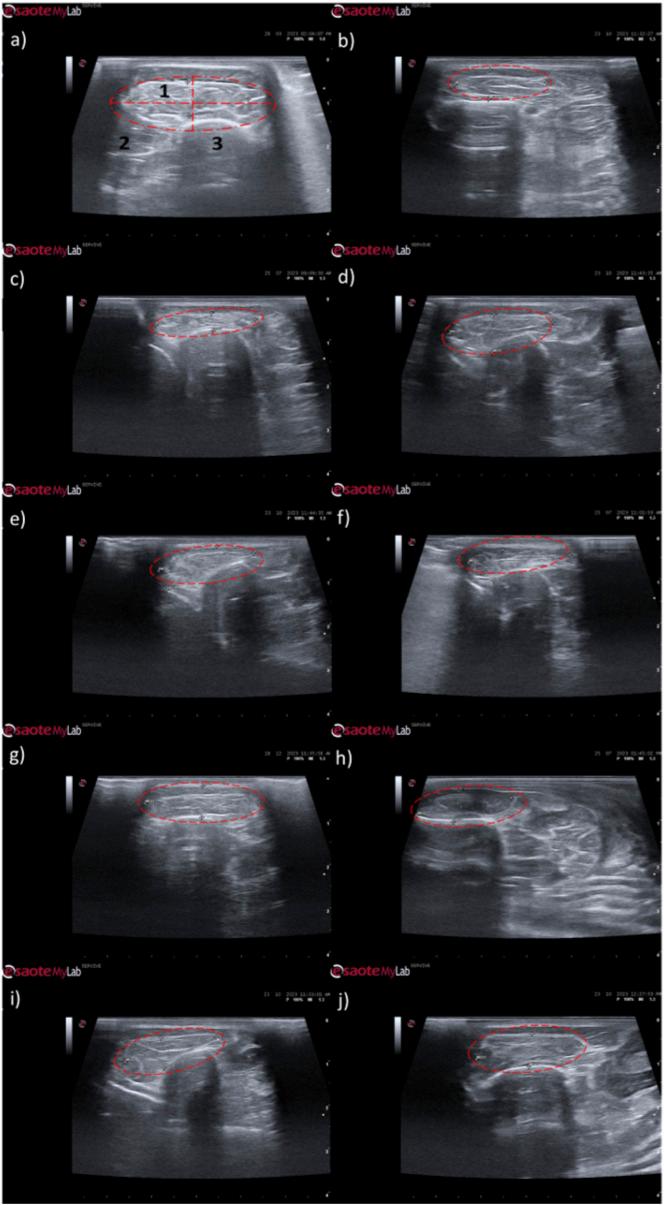

The study was conducted using a validated ovine model of common peroneal nerve injury. Recovery was assessed over 24 weeks through functional, kinematic, ultrasonographic, and electrophysiological evaluations, complemented by post-mortem nerve stereology and muscle histomorphometry.

本研究使用了经过验证的绵羊腓总神经损伤模型。通过功能、运动学、超声和电生理评估,在24周内对恢复情况进行评估,并辅以死后神经体视学和肌肉组织形态计量学。